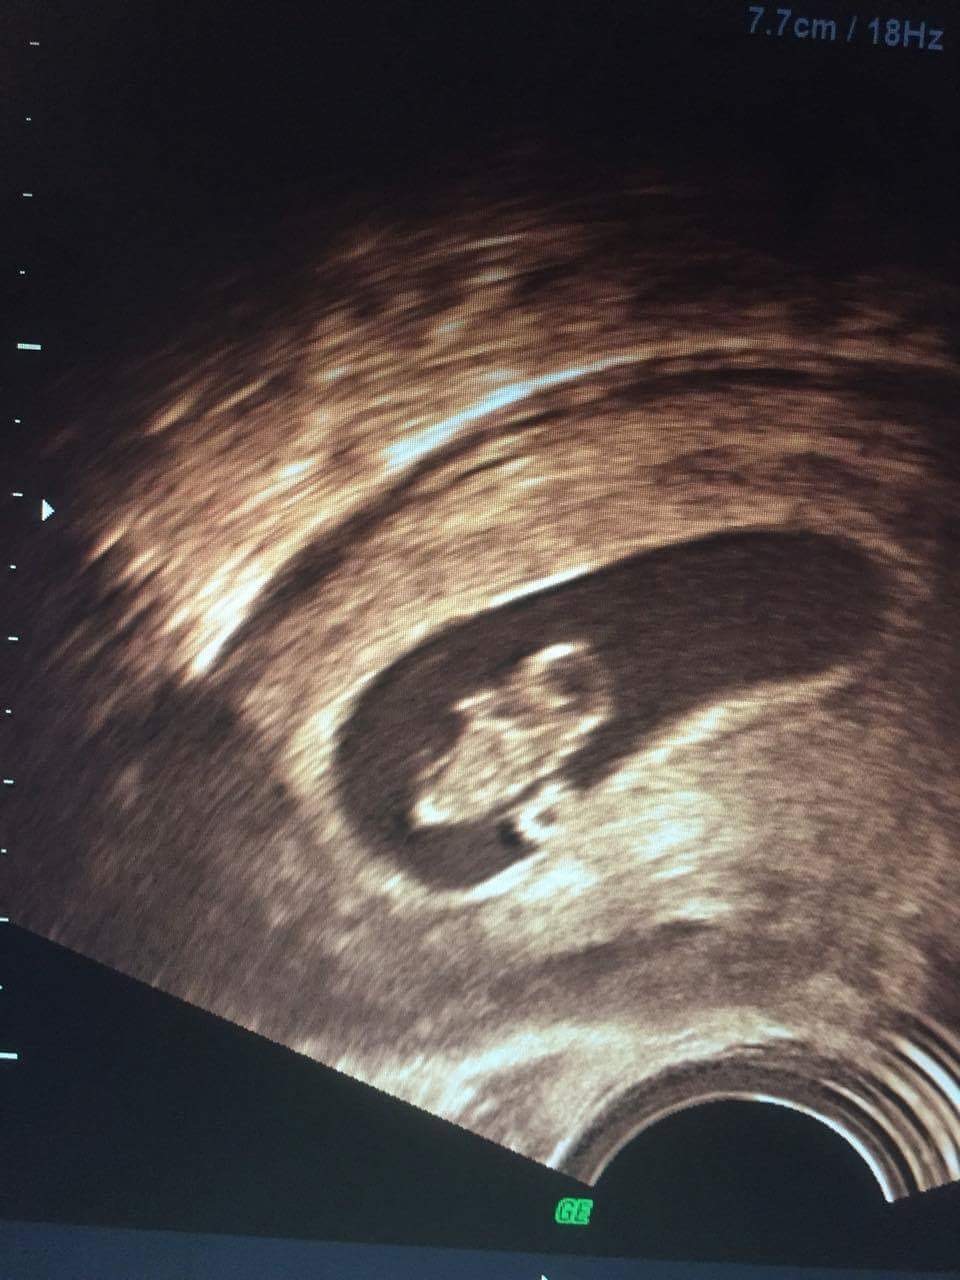

Vil bare lige vise vores lille fis frem�� Var 8+2 til scanningen i mandags og vi så fint hjerteblink, h*n var 17mm lang lille mus..